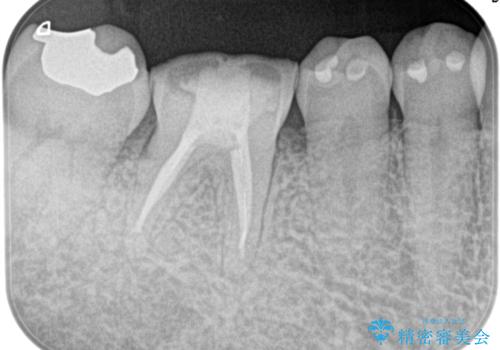

[銀歯の下の虫歯 ] 根管治療を伴う虫歯治療

![[銀歯の下の虫歯 ] 根管治療を伴う虫歯治療の症例 治療後](https://seimitsushinbi.jp/wp/wp-content/uploads/2020/05/221b5f8b0670ed2f5fe236edb26d2dc2-500x350.jpg?v=1590577586)